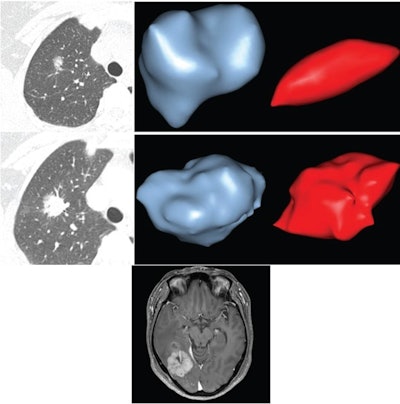

(Top left) Axial image from first chest CT examination shows part-solid nodule in right upper lobe. Diameter of whole nodule is 1.5 cm and of solid component is 0.5 cm. (Top right) Semiautomated 3D segmentations of nodule on first examination, including whole nodule (left) and solid component (right). Volume of whole nodule is 1.07 cm³ and of solid component is 0.02 cm³. Middle left: Axial image from last chest CT examination, performed 42.8 months later. Diameter of whole nodule has increased to 2.6 cm and of solid component has increased to 2.3 cm. (Middle right) Semiautomated 3D segmentations of nodule on last examination, including whole nodule (left) and solid component (right). Volume of whole nodule has increased to 5.2 cm³ and of solid component has increased to 4.4 cm³. VDTw was 565 days (less than neither 200-day or 400-day threshold), and VDTs was 168 days (less than both 200-day and 400-day thresholds). Patient underwent right upper lobectomy 1 day after last CT examination. Pathologic assessment of resected nodule yielded diagnosis of adenocarcinoma with predominant acinar histologic subtype. Pathologic stage was pT1cN0. (Bottom) Axial contrast-enhanced fat-suppressed T1-weighted image from MRI examination of brain performed 3 years postoperatively shows mass in right parietotemporal lobe; mass was resected and found to represent metastatic adenocarcinoma. Patient was confirmed to be alive 8.7 years after right upper lobectomy. VDTs=volume doubling time of solid component, VDTw=volume doubling time of whole lesion. Images and caption courtesy of the AJR.